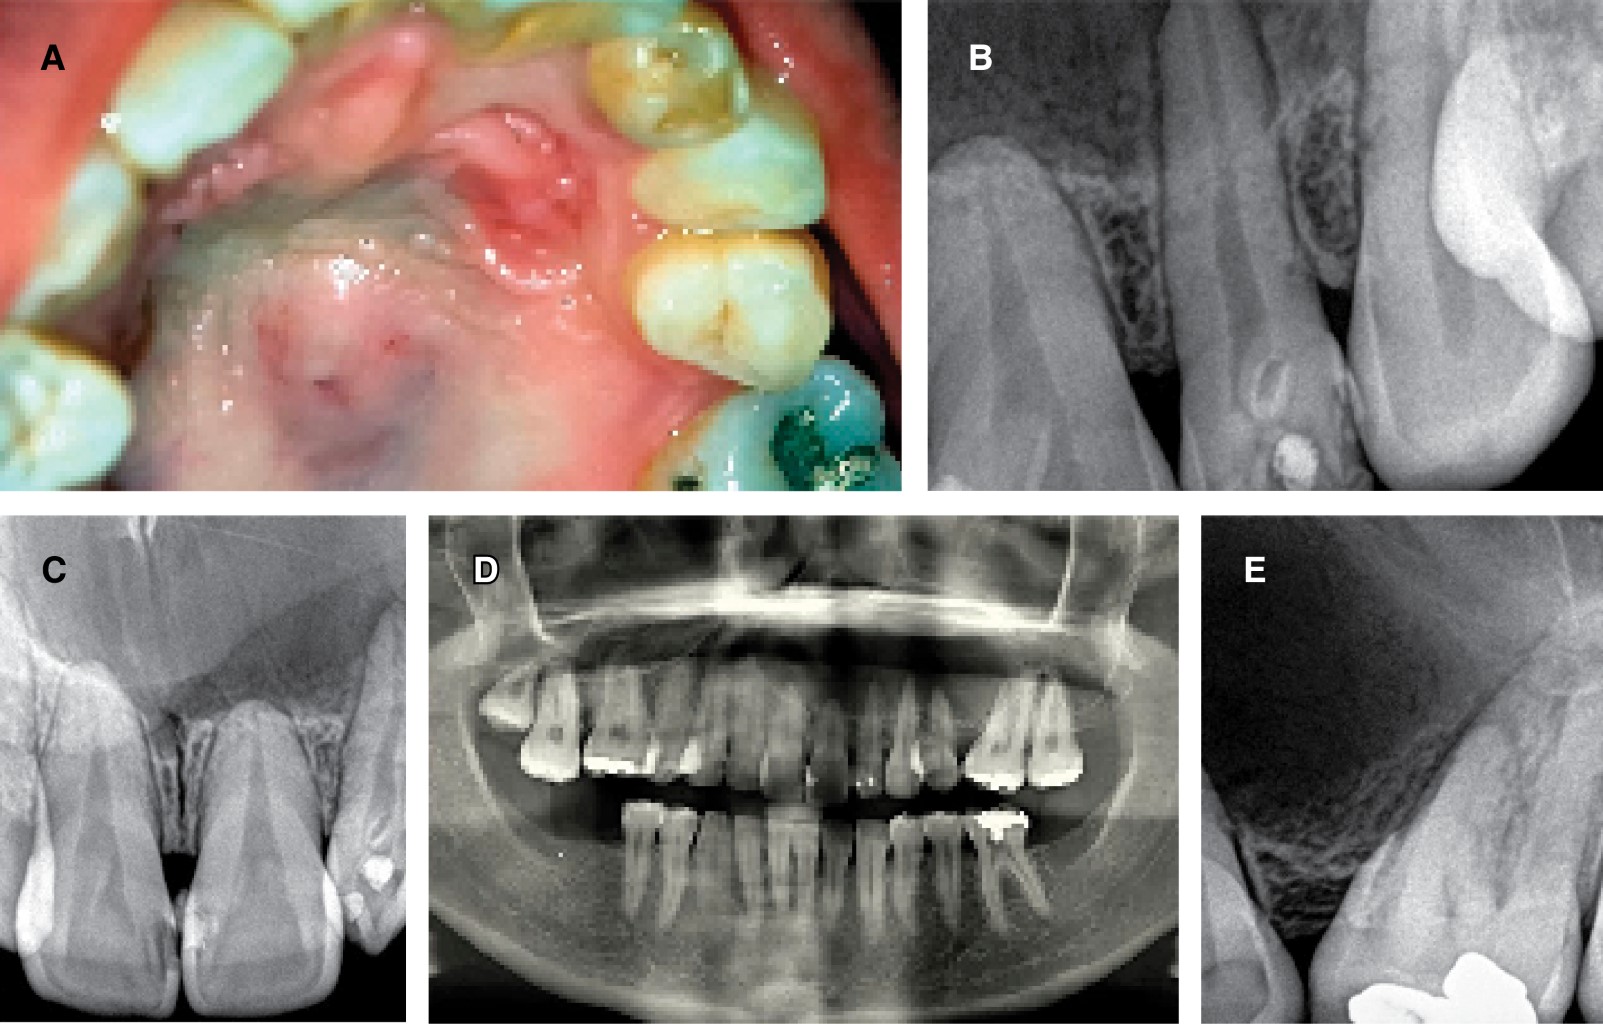

The intraoral examination revealed a slightly enlarged area in the palatal fibromucosa lateralized to the left, fluctuating, with a tendency to suppuration and pain on palpation. The provisional diagnosis was a palatal abscess, showing the upper right lateral incisor with a grayish coloration, negative pulp excitability test, and clinical suspicion of pulp necrosis. X-ray (periapical technique) showed a large radiolucent lesion in the cortex that extended beyond the areas confined to the problematic tooth (Figure 1).

In addition, as a relevant radiographic finding, a zone of radiodensity similar to dentin was observed at the level of the enamel-cementum junction, associated with an invagination of dental tissue circumscribed by a radiopaque area, compatible with DI.

An orthopantomography and a computed axial tomography showed a large lytic lesion in almost the entire left upper hemimaxilla without compromising the nasal cavity and maxillary sinus, whose anterior limit was in the corresponding central incisor sector and its posterior limit was delimited by the left first molar.

Figure 2 illustrates the different tomographic sections that allow observing the osteolytic image compatible with the cystic process. All the teeth involved showed an absence of signs of pathological rhizolysis and preserved pulp vitality, except for the left upper lateral incisor associated with DI. The clinical diagnosis was a maxillary inflammatory cyst associated with pulp necrosis of the upper lateral incisor.